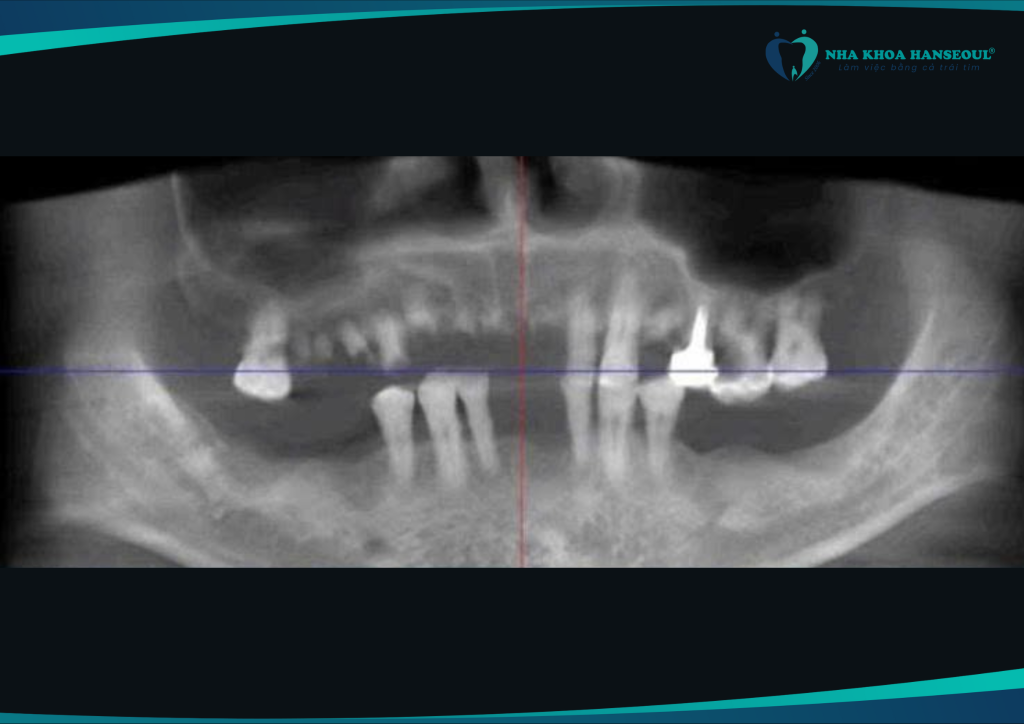

- Chụp phim CT ConeBeam 3D

- Đo mật độ xương hàm, đánh giá khả năng tích hợp trụ

Nhờ vào kết quả chi tiết này, bác sĩ có thể lập kế hoạch điều trị cá nhân hóa, đồng thời dự phòng biến chứng trong và sau phẫu thuật.